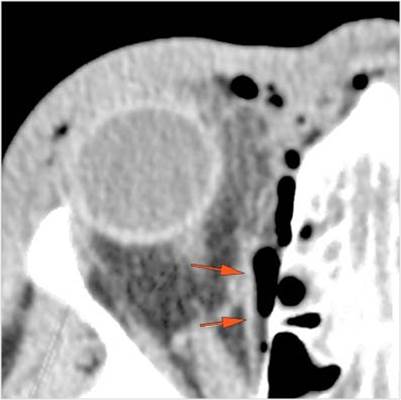

There is evidence of a subperiosteal hematoma along the medial or lateral wall, roof or floor of the orbit. [Yes/No]

There is evidence of herniated intra-orbital fat. [Yes/No]

The extraocular muscles are swollen, infiltrated or herniated into a fracture site. [Yes/No]